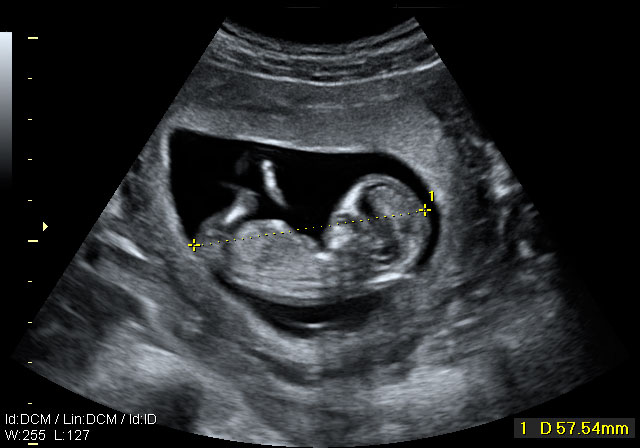

La ecografía permite medir a este feto de 12 semanas. Con esta medición se comprueba cómo crece a lo largo de las semanas. Para ello se toma la distancia que existe entre la coronilla y el final de la columna vertebral.

Embrión con una longitud de 57 milimetros,

Desde la cabeza a la rabadilla, la llamada longitud cráneo-caudal (CRL). Corresponde a 12,1 semanas de gestación.